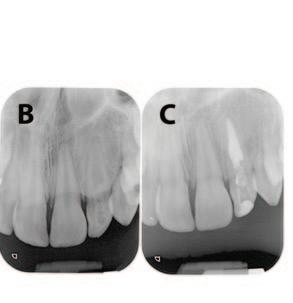

Table 1: Merged-ICDAS visual coronal caries stages.4

Merged-ICDAS score Code Description

Sound (ICDAS 0) 0

Initial caries lesions (ICDAS 1-2) A

No evidence of change in enamel translucency due to caries after plaque removal and air drying

Changes in enamel seen as a caries opacity or visible discolouration (white/brown spot) not consistent with clinical appearance of sound enamel, with no evidence of surface breakdown, no underlying dentine shadowing and no cavitation

Moderate caries lesions (ICDAS 3-4) B3

White/brown spot lesion with localised microcavity/discontinuity, without visible dentine exposure. Best seen after air drying B4 Obviously discoloured dentine visible through apparently intact or microcavitated enamel surface, which originated on the surface being evaluated. Often seen easiest with the tooth surface wet

Extensive caries lesions (ICDAS 5-6) C Obvious visible dentine cavity in opaque/discoloured enamel. A WHO/CPI/PSR probe can gently confirm if the cavity extends into dentine

2. Assess the staging of the coronal carious lesion